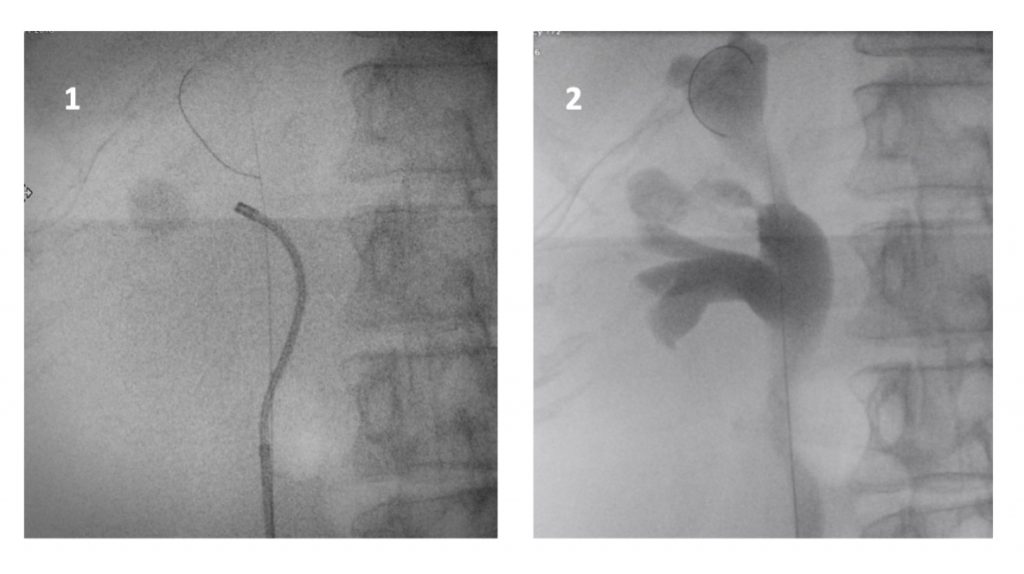

La cirugía se inicia con la instalación de un catéter ureteral externalizado. Éste permite contrastar la vía urinaria superior e identificar en la fluoroscopía, la pelvis y los cálices del riñón a tratar. Posteriormente se realiza una punción renal bajo rayos y/o dirigida por ecografía, hacia la papila renal del cáliz escogido para ingresar. Obtenido este acceso, se avanza una guía hidrofílica y se procede a la dilatación del trayecto percutáneo, lo que permitirá la instalación de una camisa (amplatz) que comunicará la piel con el cáliz y dará acceso al nefroscopio, equipo operado por el urólogo para la fragmentación y extracción de la litiasis a tratar.

Las imágenes renales son fundamentales para la planificación de la cirugía. El examen que entrega información adecuada de la morfología del paciente, anatomía renal, relaciones de órganos vecinos y características del cálculo, es la TC de abdomen y pelvis sin contraste (73). En la mayoría de los casos se puede programar la cirugía con un TC sin contraste, pero en casos seleccionados se debe solicitar un TC contrastado, con fases de excreción tardía (UroTC). En otros pacientes con atrofia cortical significativa se sugiere complementar el estudio con un cintigrama renal estático, que informe de la función renal diferencial y captación del radioisótopo por parénquima.